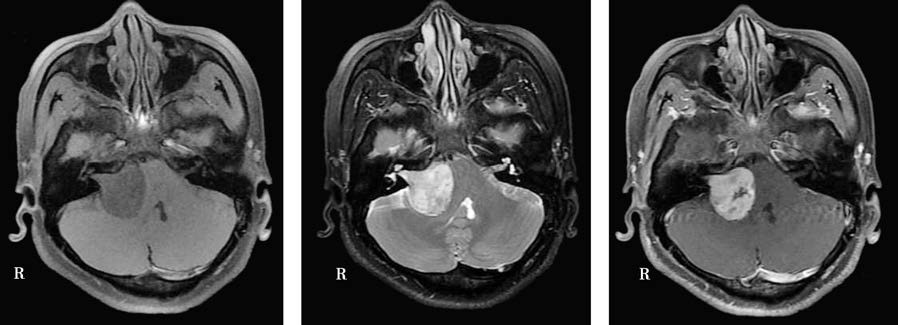

MRI is the most sensitive and effective method for diagnosing acoustic neuroma. Contrast-enhanced MRI can detect tumors as small as 1 mm in the internal auditory canal. Typical imaging characteristics include:

- T1-weighted images showing mildly hypointense or isointense signals, while T2-weighted images show hyperintense signals.

- The tumor appearing as a round or semicircular mass with an apex pointing toward the fundus of the internal auditory canal, resembling the "ice cream cone" sign.

- The tumor showing homogeneous, inhomogeneous, or annular enhancement following intravenous contrast injection, depending on the proportion and distribution of solid and cystic components within the tumor.

Figure 2 MRI findings of acoustic neuroma

A space-occupying lesion is observed in the right internal auditory canal and cerebellopontine angle. On T1-weighted imaging (T1WI), the lesion exhibits hypointense signals, while on T2-weighted imaging (T2WI), it appears hyperintense. The tumor shows significant enhancement, with portions exhibiting cystic degeneration.